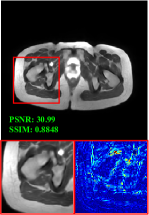

4.3 Qualitative results

Figure 5 provides the qualitative comparison of the various methods on the four datasets at a scale of 4. The top, second, third, and bottom rows are the SR results under the FastMRI, clinical brain, clinical tumor and clinical pelvic datasets, respectively. The red boxes indicate the zoom-in region of complicated anatomical structures along with their corresponding error maps. Note that the brighter textures in the error maps, the lower the quality of the reconstructed images. As can be seen, compared to methods based on Transformers and CNNs, diffusion-based methods like DisC-Diff and DiffMSR (Ours) are capable of reconstructing high-realistic images with promising reconstruction metric scores (PSNR and SSIM). Nevertheless, while DisC-Diff can reconstruct high-precision MR images, it does not preserve the structure present in the original HR images, introducing some additional information that can affect medical diagnosis. In contrast, our method combines DM and PLWformer, which can preserve the original image’s structure while restoring high-frequency information.

9 More Visual Comparisons

In this section, we present more visual qualitative comparisons. Figures 8, 9, 10, and 11 show the reconstruction results of each method in FastMRI, clinical brain, clinical tumor, and clinical pelvic, respectively. As can be seen, although DisC-Diff can reconstruct MR images with high-frequency information, it fails to preserve the structure and content of the original Target HR image effectively, resulting in image distortion. In contrast, our proposed DiffMSR can restore high-frequency information while preserving the structure of the original HR image, indicating the effectiveness of the joint use of DM and PLWformer.